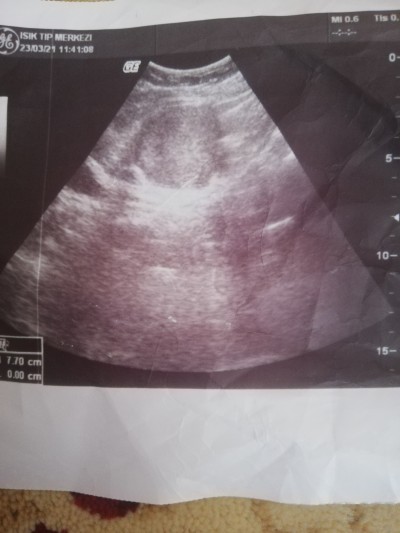

Bebek varmı resimli guzel anneler ben anlamıyorum da 6haftalık

Gebelik haftası 6haftalık

Hayır kese olusmamis

Kese yok gibi doktorunuz birşey demedi mi

Sol tarafta yarim görünen olabilir mi acaba kese?Normalde ortalayip ultrason resim alınır ama burda belli olan birşey yok.

Böyle siyah bir kabarcık olması lazım aslında hamileyseniz o kese bn ilk ultrasin fotoğrafımı yükledim 4+6 kese bu kadar 6 haftalık daha büyük oluyor ama bilemedim

Yok benimki baktığım zaman ıkı tane kese var bebek varmı yokmu anlamadım ıkı kese var dedı ama

İki mi yaa bn hiç görmedim kese baktım baktım her yer aynı gozukuyor